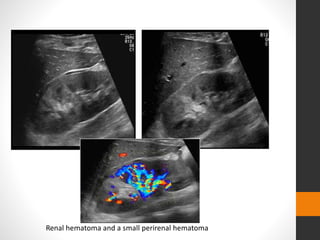

โ€ข Subcapsular and perinephric haematoma can be seen

โ€ข Acutely seen as echo-poor areas, becoming more

heterogeneous and echogenic with time.

โ€ข Disruption of renal parenchyma with capsular tears.

โ€ข Color flow and spectral Doppler may allow diagnosis of

pedicle injuries.

โ€ข Significant renal injuries may be missed, with up to 80%

of parenchymal lesions being overlooked.

Renal hematoma and a small perirenal hematoma